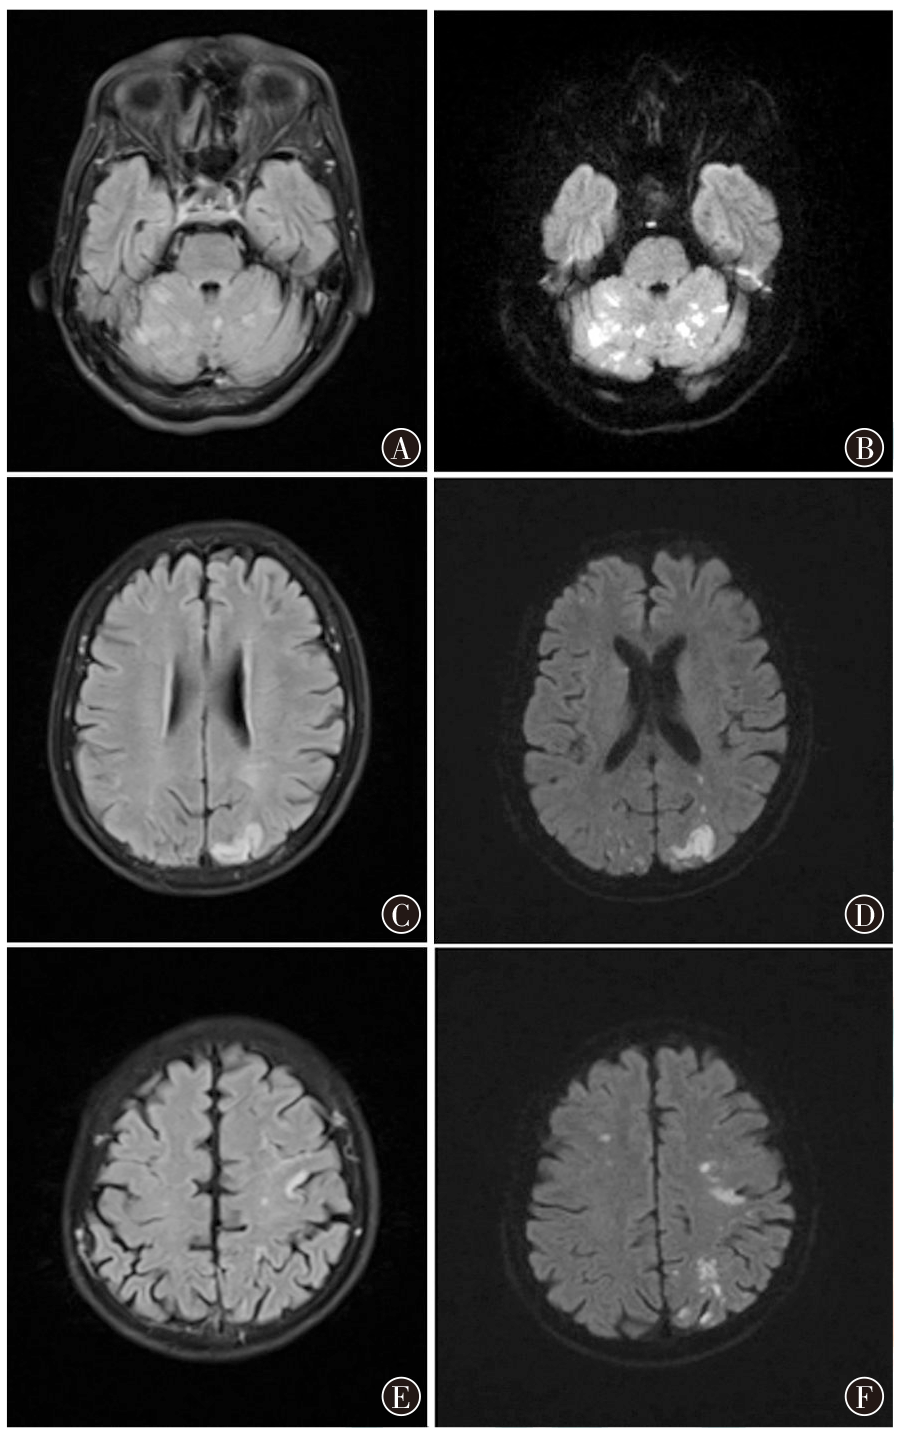

ROS1突变肺腺鳞癌合并脑梗死为主要表现的Trousseau综合征易合并血液高凝状态及多发血栓,预后不佳。现报道1例先后采用塞瑞替尼、洛拉替尼靶向治疗的ROS1突变肺腺鳞癌合并脑梗死为主要表现的Trousseau综合征,针对ROS1突变的靶向抗肿瘤治疗后获得8个月的短暂缓解,针对脑梗死采取单纯抗凝及动脉抽吸术治疗疗效不佳,靶向抗肿瘤治疗耐药后病情进展迅速,整体预后差。